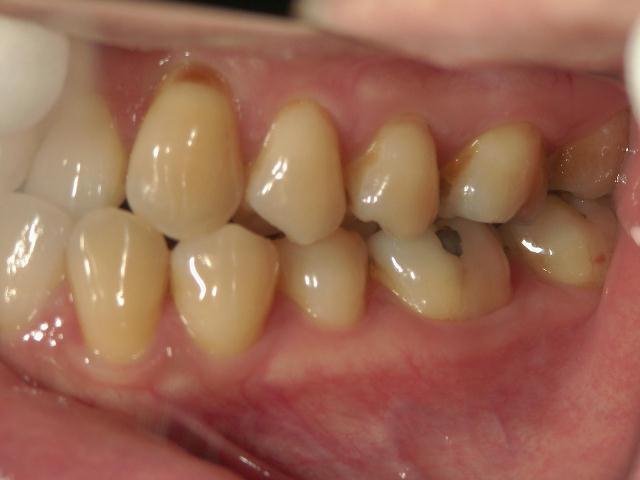

矯正歯科 治療前 右